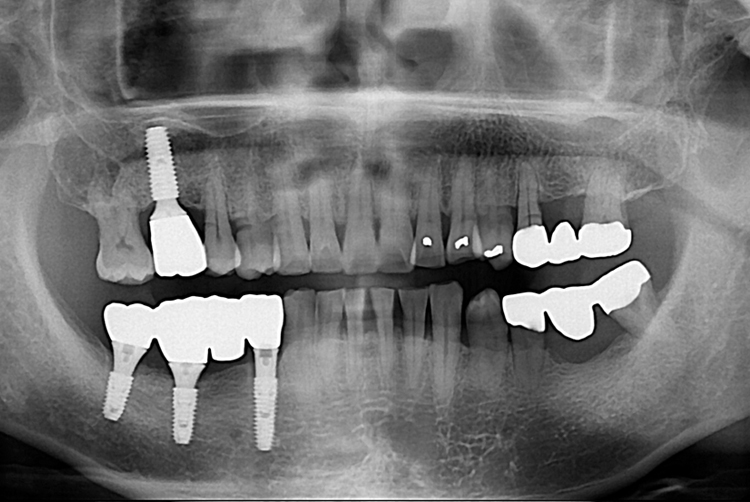

7b9b45632dccfe201ee1a98d5026be45.jpg

치료전 : 2017-10-04